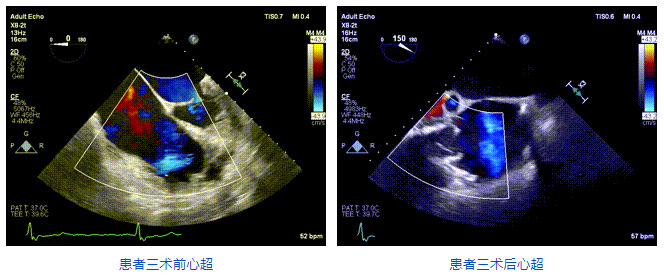

2021年12月24日,復旦大學附屬中山醫院葛均波院士團隊成功應用LuX-Valve Plus為一例極重度三尖瓣反流(TR)合并房顫、房缺的患者完成了經血管三尖瓣置換術,這是在前基礎上,本周完成的第三例經血管三尖瓣置換手術,葛均波院士、周達新教授等與心外科魏來教授、賴顥教授,心超室的潘翠珍教授、李偉教授及麻醉科的郭克芳教授共同完成了本周手術,均獲得圓滿成功!患者術后超聲顯示無TR,臨床癥狀明顯改善。本周手術的成功也為LuX-Valve Plus救治性臨床研究添上了濃墨重彩的一筆。

三例患者入院后,葛均波院士團隊周達新教授、潘文志教授、張源博士、陳莎莎博士及心超室的潘翠珍教授、李偉教授對患者的情況進行詳細評估和討論,最終決定為三例患者選擇LuX-Valve Plus40mm、50mm和50mm型號的瓣膜進行手術治療。手術后即刻拔除氣管插管,術后患者三尖瓣反流癥狀得到顯著改善,復查心超結果顯示人工三尖瓣瓣膜支架固定穩定,瓣葉關閉形態未見異常,未見明顯反流。